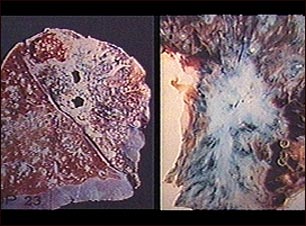

Tuberculosis pulmonar

La tuberculosis es causada por un grupo de organismos: Mycobacterium tuberculosis, M. bovis, M. africanum y otros subtipos menos comunes. Por lo general infecta los pulmones, pero puede afectar otros órganos del cuerpo. Recientemente han aparecido cepas de tuberculosis resistentes a los antibióticos. Hoy en día, debido al número creciente de individuos inmunocomprometidos con SIDA, y de indigentes sin cuidado médico, los casos de tuberculosis han ido en aumento. (Cortesía de los Centros para el Control y la Prevención de Enfermedades -CDC- de los Estados Unidos)